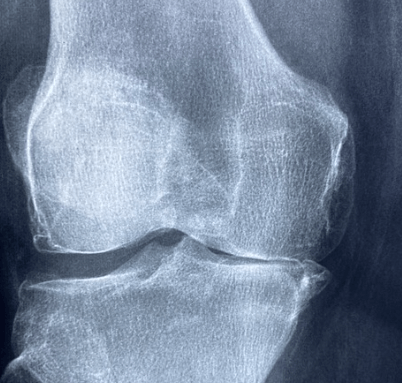

6) 골관절염 진행 억제

연구에 따르면, 골관절염의 진행을 늦추는 데 도움이 될 수 있다고 합니다. 이는 연골 손상을 최소화하고, 장기적으로 관절의 건강을 유지하는 데 기여한답니다.